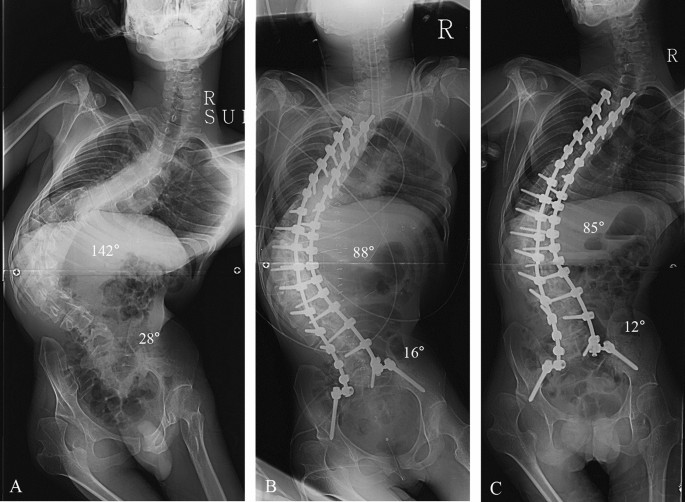

This study was designed as retrospective, comparative analysis at a single institute where deformity correction was routinely performed. All deformity correction procedures were performed by a senior spine surgeon with vast experience in performing standard open surgeries. Considering the effect of pelvic fixation on surgical outcomes, we enrolled patients with NMS who underwent deformity correction from 2009 to 2016. Patients with Cobb’s angle less than 40º and/or PO less than 15º were excluded in our study. A total of 77 patients was included and divided into three groups as follows: the pelvic fixation group (n = 16, NMS patients who underwent pelvic fixation) (Fig. 1), fixed to S1 group (n = 33, NMS patients who underwent fixation to S1 without pelvic fixation) (Fig. 2), and fixed to L5 group (n = 28, NMS patients who underwent fixation to L5 without pelvic fixation) (Fig. 3). This study was performed after obtaining approval of the institutional review board of Korea University of Guro Hospital. The present study was performed in accordance with the contemporary amendments of the Declaration of Helsinki and within an appropriate ethical framework. Both children and parent and/or legal guardians were informed of the purpose of the study, agreed to participating, and signed informed consent for both study participation and publication of identifying information/images in an online open-access publication.

Deformity correction from T3 to spinopelvic fixation using iliac screw in patients with neuromuscular scoliosis (NMS). (A) A 27-year-old male patient who diagnosed with cerebral palsy (spastic quadriplegia) showed NMS. The whole-spine anterior–posterior image showed 142° of scoliosis deformity, and pelvic obliquity was 28° as measured by pelvic tilting angle. (B) The immediate postoperative radiograph showed 88° of the Cobb’s angle (61.4% of correction rate) and 16° of the pelvic tilting angle (42.9% of correction rate from the spinopelvic fixation). (C) The 2-year follow-up Cobb angle was 85° and pelvic obliquity was 12°.